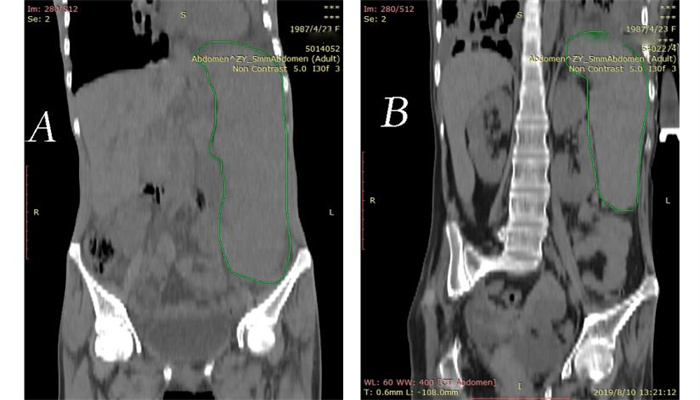

| A、B为患者在同样CT设备,同样扫描厚度,同一影像序列(280)腹部正位CT图像。A:患者入院腹部CT,提示巨脾,脾脏最大径为136.000 mm,体积是1 755.064 mm3;B:患者复查腹部CT,脾脏最大径为104.000 mm,体积是641.545 mm3。 图 2 患者腹部CT图像 |

患者女,31岁,因“咳嗽、咳痰伴腹胀3 d”于2019年2月4日转诊至遵义医科大学附属医院。入院前3 d,患者咳嗽、咳痰,发热39℃,伴腹胀、腹痛,就诊当地医院,考虑“肺部感染、脾大”,予抗感染治疗,无好转遂转院。患者既往史、个人史及流行病学史无特殊。查体:呼吸34次/min,体温39 ℃。双肺闻及湿性啰音,左腹部及脐周压痛,肋缘下10 cm触及脾脏,越过前正中线。胸部CT示支气管扩张并双肺感染,腹部CT示巨脾,体积1 755.064 mm3。白细胞(WBC)2.24×109/L,红细胞(RBC)2.71×1012/L,血小板(PLT)67×109/L,C反应蛋白(CRP)73.60 mg/L。入院诊断:(1)脓毒症、支气管扩张并感染;(2)三系(WBC、RBC、PLT)减少,原因:脾功能亢进;(3)巨脾。诊断依据:(1)患者临床表现及病史;(2)检查、检验结果;(3)sepsis 3.0,SOFA评分大于2分;(4)结核检测及胸部CT排除结核分枝杆菌感染,骨髓穿刺结果不支持血液及淋巴系统疾病,回顾患者既往病史及腹部CT图像排除肝硬化等疾病。多学科会诊:针对巨脾,考虑脓毒症所致充血性肿大,不考虑肝硬化及班替氏综合征,继续抗感染治疗, 菌培养+药敏结果提示哌拉西林舒巴坦钠、盐酸莫西沙星敏感的金黄色葡萄球菌,最终诊断:(1)脓毒症;(2)支气管扩张并感染;(3)巨脾;三系减少病因:脾功能亢进。再次根据药敏试验调整抗生素,患者体温恢复正常,脾脏体积出院时仅有641.545 mm3, 三系终于恢复正常范围,感染指标下降,好转出院。

脓毒症是炎症反应失衡引起的危及生命的器官功能障碍[1],早期表现为全身炎症反应综合征(SIRS),最常见的病因是肺部感染,而其最早的器官功能障碍亦体现于肺部[2-3]。支气管扩张是支气管壁肌肉及弹性组织破坏的结果,因其引流不畅的结构特点,临床表现为反复呼吸道感染[4],病原菌以革兰阴性杆菌为主[5],而临床反复及不合理应用抗生素,产生耐药菌,耐药病原持续刺激机体产生免疫风暴,炎症反应失衡,最终发展为脓毒症。本例患者血培养两次培养出耐甲氧西林金黄色葡萄球菌,胸部CT提示支气管扩张并肺部感染,体温大于39℃,脾功能亢进,血小板 < 70×109 /L,患者SOFA评分为2分,根据sepsis 3.0诊断标准, 诊断为脓毒症。脓毒症可导致机体器官功能障碍。研究表明,脓毒症患者的脾细胞有高度的功能性损伤[6];动物实验表明,厌氧菌致肝脓肿家兔的脾脏严重肿大,呈暗紫色[7]。脾脏作为最大的外周免疫器官,其介导的炎症反应在SIRS的肺部表现-创伤性急性呼吸窘迫综合征中有重要作用[8]。脾大常见的病因为感染[9], 脾脏是减轻脓毒症炎症反应的关键器官[10]。本例患者入院脾脏体积达1 755.064 mm3,越过前正中线,根据Hackett的触诊标准[11],为极度脾肿大(V级)[12],经抗感染治疗,脾脏缩小至641.545 mm3。临床上引起脾大的疾病众多,如感染性疾病、血液病、消化系统疾病、免疫病、肿瘤、结缔组织病等[13],现有研究多与脾源性炎症反应及病因机制相关,关于脾脏体积变化与病情相关性少有报道,而脾大至本病例程度者暂未发现。炎症所致脾大,实质为脾脏白区的增生扩张,表明免疫活动活跃[9],小鼠脑卒中后,脾脏先增大后减小,考虑与脾脏炎症介质及细胞的产生释放至全身的过程密切相关[14]。脾大使脾脏的血细胞吞噬破坏功能增强,是三系减少的原因之一,通过治疗原发病,脾脏恢复正常,三系水平自然恢复。因此,处理原发病是治疗脾大及其并发症的关键。

本例患者因肺部感染起病,发展至脓毒症,并发巨脾、三系减少等症状,临床经积极抗感染治疗原发病,患者巨脾消退近三分之二,而随巨脾症状缓解,患者三系恢复正常。本例脓毒症所致巨脾体积之大,并发的一系列临床症状均可因原发感染治愈而好转、消失,由此为脓毒症所致脾脏相关并发症和脾脏介导炎症反应的相关研究提供临床案例。